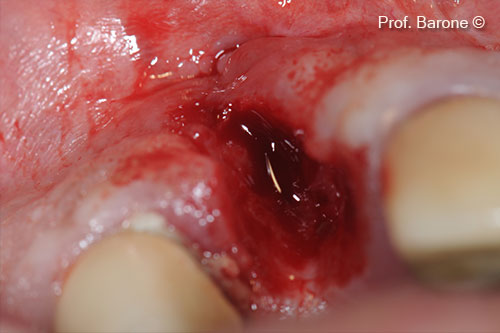

Tooth Extraction

Fresh Extraction socket treated with collagen sponge and cross-suture